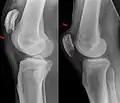

Quadriceps tendon rupture in plain X-ray

X-ray of a tear of the patellar tendon. On the left: The kneecap is pulled up. On the right: Significant dent in the soft tissue above the kneecap.